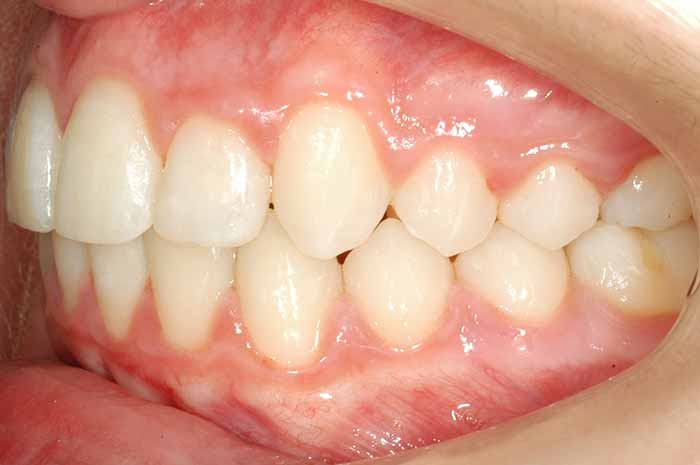

Tratamiento realizado:

Ortodoncia convencional con brackets metálicos

En este caso, para conseguir un resultado óptimo, también se utilizó un aparato removible (de quita y pon) en la arcada superior, previo a la colocación del aparato fijo (brackets).

La excepcional colaboración de la paciente fue fundamental para la consecución de los resultados.

Antes y Después